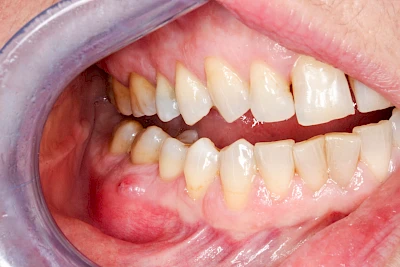

Diese Vermehrung von Bindegewebe in einem frei gewordenen Raum ist eine Sonderform der Anpassungsreaktion menschlicher Zellen und wird als Vakatwucherung bezeichnet.

Früher wurden im Unterkiefer mitunter Brücken zum Ersatz fehlender Zähne als sogenannte "Schwebebrücken" gestaltet. Die Idee dabei war, dass man die Brücke insgesamt besser reinigen kann. Allerdings war das für die Patienten mitunter irritierend für die Zunge und vor allem beim Essen gewöhnungsbedürftig. Teilweise haben sich hier reaktiv Vakatwucherungen der Kieferkammschleimhaut gebildet und den Raum unter der Brücke wieder verschlossen.